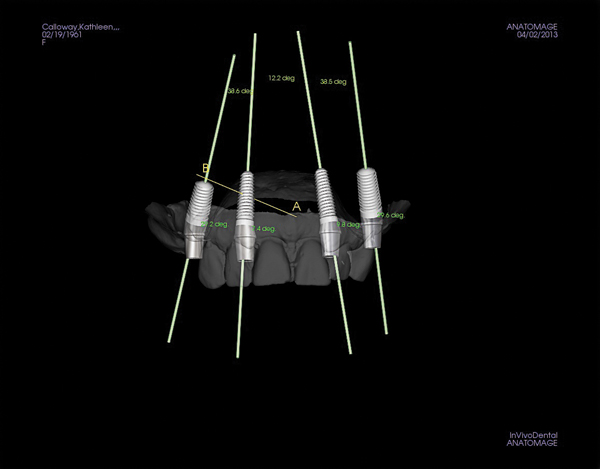

Figure 3 Examples of using digital workflow to import restoration data and plan implant treatment: the intraoral scan (IOS) data pinned to the CBCT (Fig 3); the designed ideal restoration being imported into the CBCT (Fig 4); the implant placed with the restoration and IOS toggled off (Fig 5).

Figure 4 Examples of using digital workflow to import restoration data and plan implant treatment: the intraoral scan (IOS) data pinned to the CBCT (Fig 3); the designed ideal restoration being imported into the CBCT (Fig 4); the implant placed with the restoration and IOS toggled off (Fig 5).

Figure 5 Examples of using digital workflow to import restoration data and plan implant treatment: the intraoral scan (IOS) data pinned to the CBCT (Fig 3); the designed ideal restoration being imported into the CBCT (Fig 4); the implant placed with the restoration and IOS toggled off (Fig 5).

Figure 6 Implants and abutments placed, with the model turned off and the CBCT in view.

Figure 7 Implants and abutments in place with pinned model scan and CBCT off.

Although workflows can vary, in many implant cases, typically a CBCT scan of the area of concern is made. Then, with an intraoral scan or digital version of a model or impression, the practitioner begins working with the design software of the particular intraoral scan or CBCT system being used (Figure 3 through Figure 5). The edentulous area or area where teeth are to be extracted can then be thoroughly evaluated. Ideal restorations can then be previsualized or treatment planned from both an esthetic and functional standpoint. Once this is done, the intraoral information is pinned or overlaid onto the CBCT scan. The restoration(s) can then be imported into the software system, toggled on or off—ie, shown or not—and the underlying bone evaluated.3

If the ideally designed restorations cannot be supported by available bone, additional surgical procedures, such as grafting, may be indicated. Implants can be placed in 3-D in the ideal location for esthetics and function, allowing the practitioner to visualize where osseous grafting may be needed to achieve that positioning. Alternatively, implants can be virtually positioned based on the available anatomy, respecting anatomical structures such as the inferior alveolar nerve, maxillary sinus, and the buccal/lingual plates (Figure 6 and Figure 7). This restorative-driven implant placement workflow allows general practitioners to see what may be needed to augment bone to support ideal restorations. This may alert them to the need for additional surgical procedures or to open further dialogue with surgical team members.